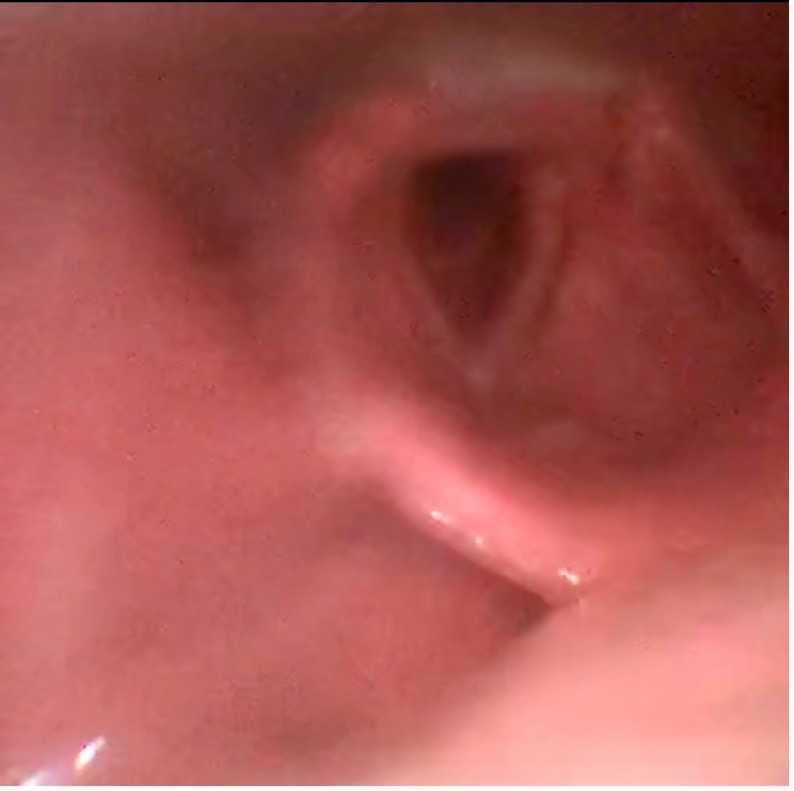

His initial workup consisted of close airway observation with end-tidal capnometry, rapid strep test, throat culture, respiratory pathogens PCR, and a neck X-ray. A bedside nasopharyngoscopy was conducted; it showed crisp tonsillar structures and no laryngeal edema. A diagnosis of uvulitis was given.

Figure 2. Still image captured from nasopharyngoscopy showing no laryngeal edema. (Click to enlarge.)

Figure 3. Still image captured from nasopharyngoscopy showing crisp vocal cords and tonsillar fornixes. (Click to enlarge.)